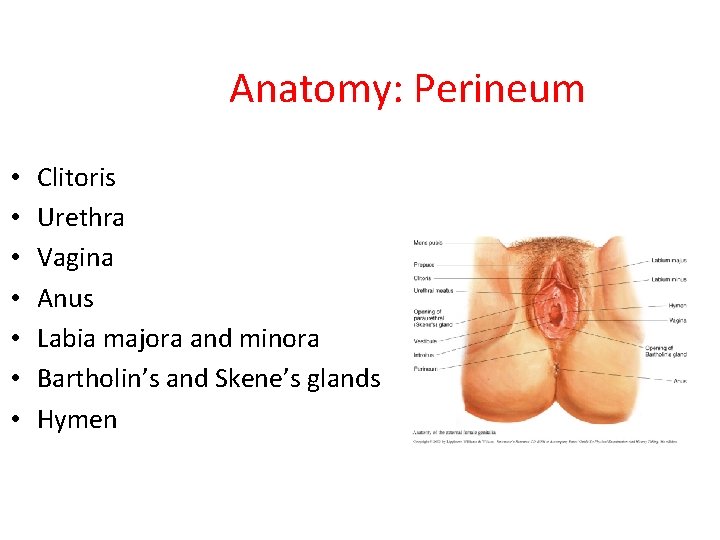

Anatomy: Perineum • • Clitoris Urethra Vagina Anus Labia majora and minora Bartholin’s and Skene’s glands Hymen

EKSTERNAL ACCESSORY ORGANS (Vulva – Pudendum) Mons pubis Labium majus Labium minus Clitoris Bulbus vestibuli Gl. vestibularis major • Gl. vestibulares minor • • •

Labium Majus Pudendi • • • Correspond to the scrotum Includes numerous hairs Rima pudendi Commisura labiorum ant. Commisura labiorum post. Lig. rotundum Rima pudendi Commissura post

Labium Minus Pudendi (Nymphae) • • Includes sweat glands Preputium clitoridis Frenilum clitoridis Sulcus nympholabialis Frenulum labiorum pudendi Fossa navicularis Fourchette Sulcus nympholabialis Frenulum labiorum pudendi Frenulum clitoridis

Clitoris • Corresponds to the male penis • Corpus, crus, glans • Attach to the side of the pubic arch with Lig. Suspansorium

Vestibüle - Introitus (Vestibulum Vaginae) • The Vaginae and ostium urethra externa opens vestibüle • Covered by stratified squamous epithelium Vestibül

Glandula Vestibularis Major (Bartholin’s glands) • Correspond to the male bulbourethral glands • Covered by M. bulbocavernosus • Secrete fluid that moistens and lubricates vestibule

Glandula Vestibularis Minor (Skene glands) • Opening either side of the urethra • To get Gonore retansiyon abscess Skene kanalları

Hymen Feminus • Mucosal fold • Carunculae myrtiformis